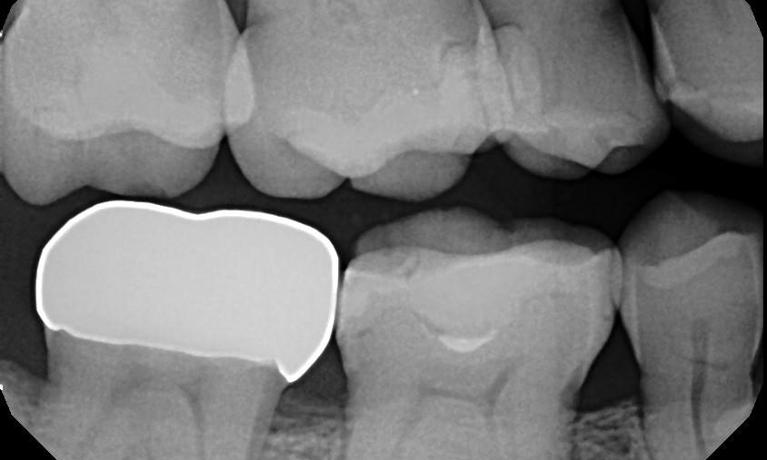

A deep cleaning is needed when tarter buildup is in excess throughout the mouth. Often times the bone levels are lower and gum tissues are swollen and bleed more easily. This is due to the abundance of bacteria present that is concentrated in the tarter. Deep cleanings remove not only the tarter (seem in the before photo), but also the bacteria that prevents your mouth to be healthy. Usually because of the amount of tarter buildup the dental hygienist need to numb the area for the patients comfort.

During a regular dental cleaning plaque and tarter are removed from the teeth. Having this slight buildup that occurs every 6 months removed from the teeth, helps keep the gums and the surrounding bone healthy and strong. If left for too long, this plaque and tarter will form under the gum tissue and a deeper cleaning will be needed.